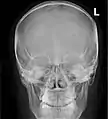

![]() Paranasal sinuses seen in a frontal view | |

Paranasal sinuses radiograph (occipitomental)